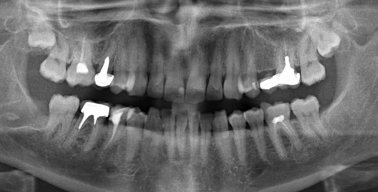

Сутки назад поставил коронку на живой зуб (жевательный снизу), до установки коронки зуб не болел. До установки пломба была большой и отвалилась часть стенки зуба, врач-стоматолог посмотрел снимок и сказал, что лучше ставить на живой зуб, так как воспалений и всяческих патологий нет, зуб лучше сохранить, коронка цирконий!

Такое случается, но острой боли быть не должно. Скорее всего, чувствительность не пройдет, а будет усиливаться, так как при обточке зуб уже реагировал на внешние факторы. Покажитесь врачу, сделайте рентген и картина будет ясна.